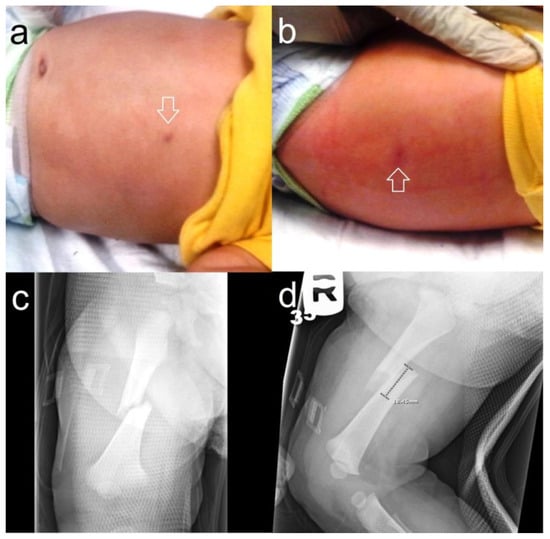

Figure 4. A nine-month-old was brought in for excessive irritability. Upon physical examination, there were two circular, healing burn marks on the abdomen (a) and back ((b), arrows) later proven to be from cigarette burns. A radiological workup and skeletal survey showed a right femoral fracture (c,d), but no other osseous anomalies.